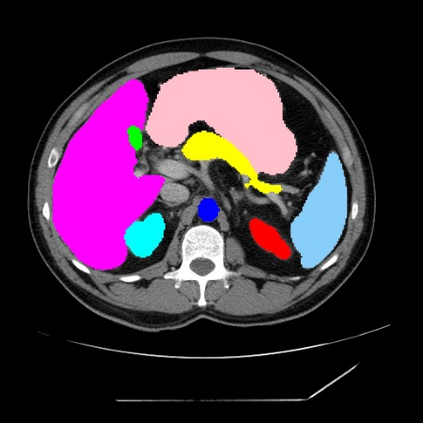

Integrating high-level semantically correlated contents and low-level anatomical features is of central importance in medical image segmentation. Towards this end, recent deep learning-based medical segmentation methods have shown great promise in better modeling such information. However, convolution operators for medical segmentation typically operate on regular grids, which inherently blur the high-frequency regions, i.e., boundary regions. In this work, we propose MORSE, a generic implicit neural rendering framework designed at an anatomical level to assist learning in medical image segmentation. Our method is motivated by the fact that implicit neural representation has been shown to be more effective in fitting complex signals and solving computer graphics problems than discrete grid-based representation. The core of our approach is to formulate medical image segmentation as a rendering problem in an end-to-end manner. Specifically, we continuously align the coarse segmentation prediction with the ambiguous coordinate-based point representations and aggregate these features to adaptively refine the boundary region. To parallelly optimize multi-scale pixel-level features, we leverage the idea from Mixture-of-Expert (MoE) to design and train our MORSE with a stochastic gating mechanism. Our experiments demonstrate that MORSE can work well with different medical segmentation backbones, consistently achieving competitive performance improvements in both 2D and 3D supervised medical segmentation methods. We also theoretically analyze the superiority of MORSE.

翻译:在医学图像分割中,整合高级语义相关的内容和低级解剖特征对于模拟这些信息非常重要。近期基于深度学习的医学分割方法已经显示出很有前景,可以更好地建模这些信息。然而,医学分割的卷积运算符通常在正则化网格上运作,这在本质上模糊了高频区域,即边界区域。我们在这项工作中提出了 MORSE,这是一个设计在解剖学水平上的通用隐式神经渲染框架,用于协助医学图像分割的学习。我们的方法的动机在于隐式神经表示已经被证明比离散化网格表示更有效地拟合复杂信号和解决计算机图形问题。我们方法的核心是将医学图像分割连续地对准粗糙的分割预测和模棱两可的基于坐标的点表示,并聚合这些特征来自适应地精细化边界区域。为了并行地优化多尺度像素级特征,我们借鉴了 Mixture-of-Expert (MoE) 的思想设计和训练我们的MORSE,使用随机门控机制。我们的实验表明MORSE可以很好地与不同的医学分割后骨干结合在一起,始终在2D和3D监督医学分割方法中实现了有竞争力的性能改进。我们还从理论上分析了MORSE的优越性。